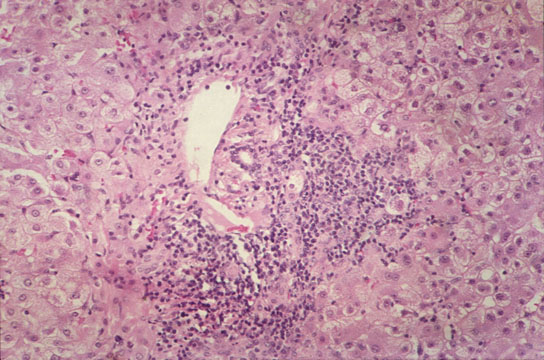

Central vein endophlebitis

Fig 56 - CENTRAL VEIN ENDOPHLEBITIS: In a case of fulminatinaute viral hepatitis..